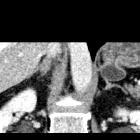

CT/MRI

A well defined saccular collection of fluid or gas that demonstrates communication with the gastric cavity (fills with iodinated oral contrast on CT).

In cross-sectional studies gastric diverticula can mimic a left adrenal mass. In fluoroscopic studies, they may mimic a gastric ulcer.